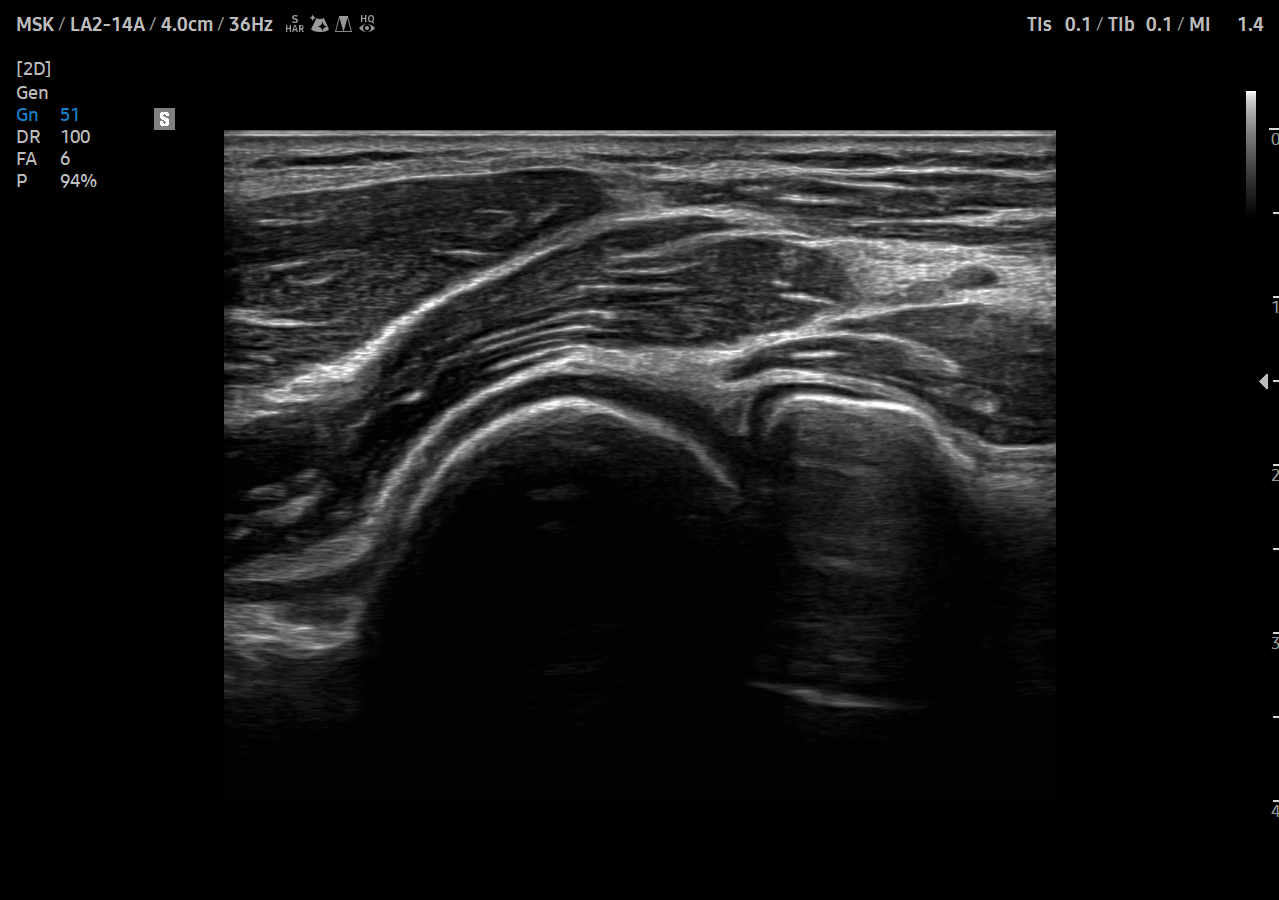

Calitate excelentă a imaginii pentru o mai mare fiabilitate și siguranță

Obțineți informații detaliate bazate pe performanța remarcabilă a imaginii, alimentată de motorul principal de imagine al Samsung, Crystal Architecture. Motorul de imagistică premium combină beneficiile procesării avansate a imaginilor 2D și expresia detaliată a procesării semnalului de culoare.

ShadowHDR aplică în mod selectiv ultrasunetele de înaltă sau joasă frecvență pentru a identifica zonele întunecate, cum ar fi capul sau coloana vertebrală a fătului, unde verifică atenuarea și compensează acestea permițând o mai mare vizibilitate a țesăturii.

HQ-Vision oferă imagini mai clare prin atenuarea zonelor de imagine care sunt mai neclare decât natura lor reală

Filtrul de reducere a zgomotului îmbunătățește definiția marginilor și creează imagini 2D clare pentru performanțe optime de diagnosticare. În plus, ClearVision oferă optimizare specifică aplicației și rezoluție temporală avansată în modul de scanare în timp real.